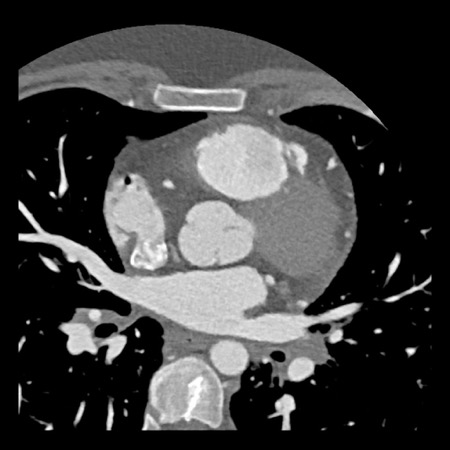

case 3 – Calcium score 0 and severe stenoses.

First, scroll through the CTA images.

How would you describe the findings on the coronary CTA?

The findings are:

- The total calcium

score of 0 indicates the absence of calcified plaque in the coronary

tree. - Severe stenosis

(70-99%) in the mid LAD and D2 branch.

Continue with the next images of the same patient…

Same patient. First, study the CTA image.

How would you describe the findings?

The coronal image shows a central low-attenuation area around the lumen

of the LAD.

This low-attenuation area is surrounded by a higher attenuation

area.

This finding is the earlier discussed napkin-ring sign, which is a high-risk

plaque feature.

This patient classifies as CAD-RADS 4A/P1/HRP.